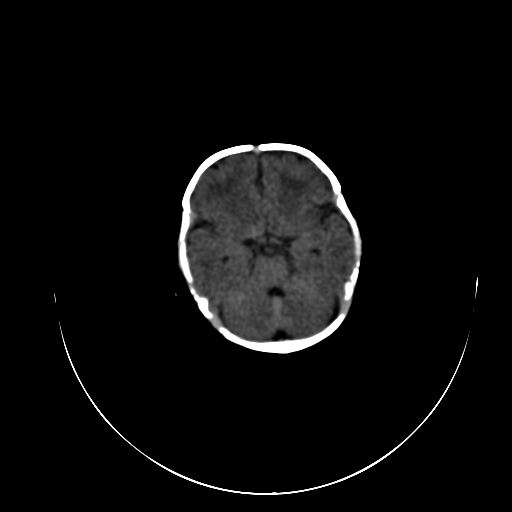

标题: PED0840:女,1.6岁,全身粘膜黄染6天,医生考虑新生儿胆红素 [打印本页]

标题: PED0840:女,1.6岁,全身粘膜黄染6天,医生考虑新生儿胆红素

正常  机器伪影

双侧脑实质多发低密度灶;是图象燥声?烟雾病?         右基底节到顶叶高密度灶,长轴大于宽度,伪影?出血灶??

机器伪影,每层都有,如果是病灶那不成了园柱形的了吗

每层都有且没有改变,应该是机器伪影。

谢谢拉,经过第二次扫描,就没有看见了,

开始我们也怀疑是机器伪影,但又怕是其他的。

不敢下结论。